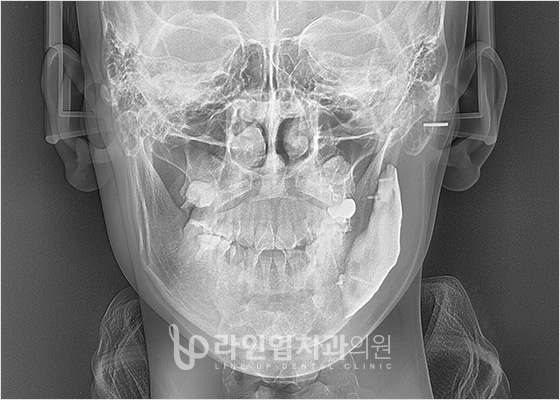

01 Компьютерная томография 3D

Система высокоточной трехмерной диагностики

позволяет в точности проанализировать не только лицевые кости, но и лицевые нервы, кровеносные сосуды и их расположение, а так же состояние мышц и жировой ткани, вплоть до строения и движения лицевых костей.

Изготовление точно подходящих костных имплантатов

идеально подходящий имплантат под форму кости пациента, в точности повторяющий поверхность кости